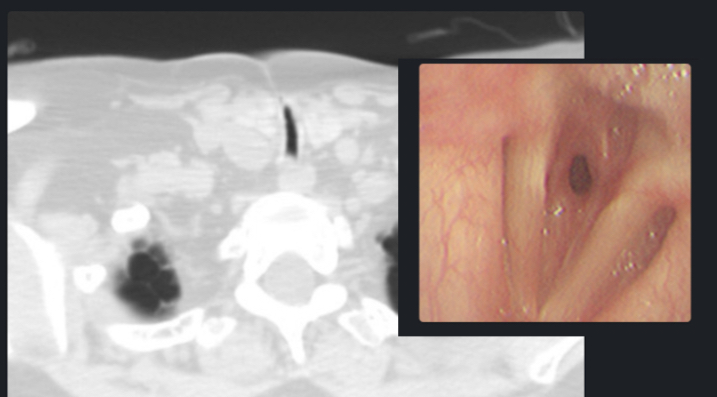

Sténoses Mécaniques

Général

- Post Intubation++

- Post Tube de Trachéostomie

- La pression du ballonet (+irritation, stéroides etc) → Nécrose de la muqueuse

- Les manchons basse pression sténosent moins (1%) que les haute pression (20%)

- TTT: Dilatation à l’Endoscopie Rigide ± Stent ou Traitement Laser YAG (Neodymium yttrium aluminium garnet ), Chirurgie si sténose complexe

Imagerie

- Souvent Ratée car en zone en bordure supérieure de la radio !